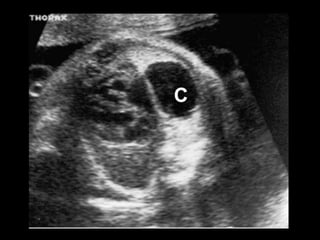

Sequestro intralobar com infecções recorrentes

Sequestro intralobar cominfecções recorrentes